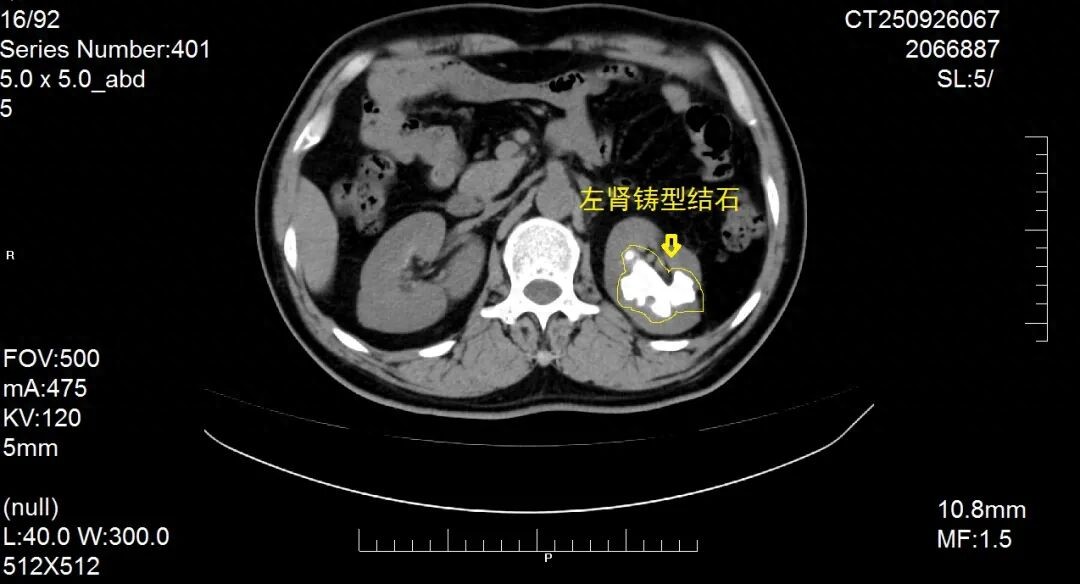

患者因“反复肉眼血尿1月,再发加重1周”入院,经系统检查确诊为复杂性肾结石

该患者结石体积大、负荷高,且合并肾内结构变异,常规微创治疗难度极高。科室团队经全面评估后,决定另辟蹊径,摒弃微创手术需反复多次取石的不足,采用传统的开放肾盂肾实质切开取石术。